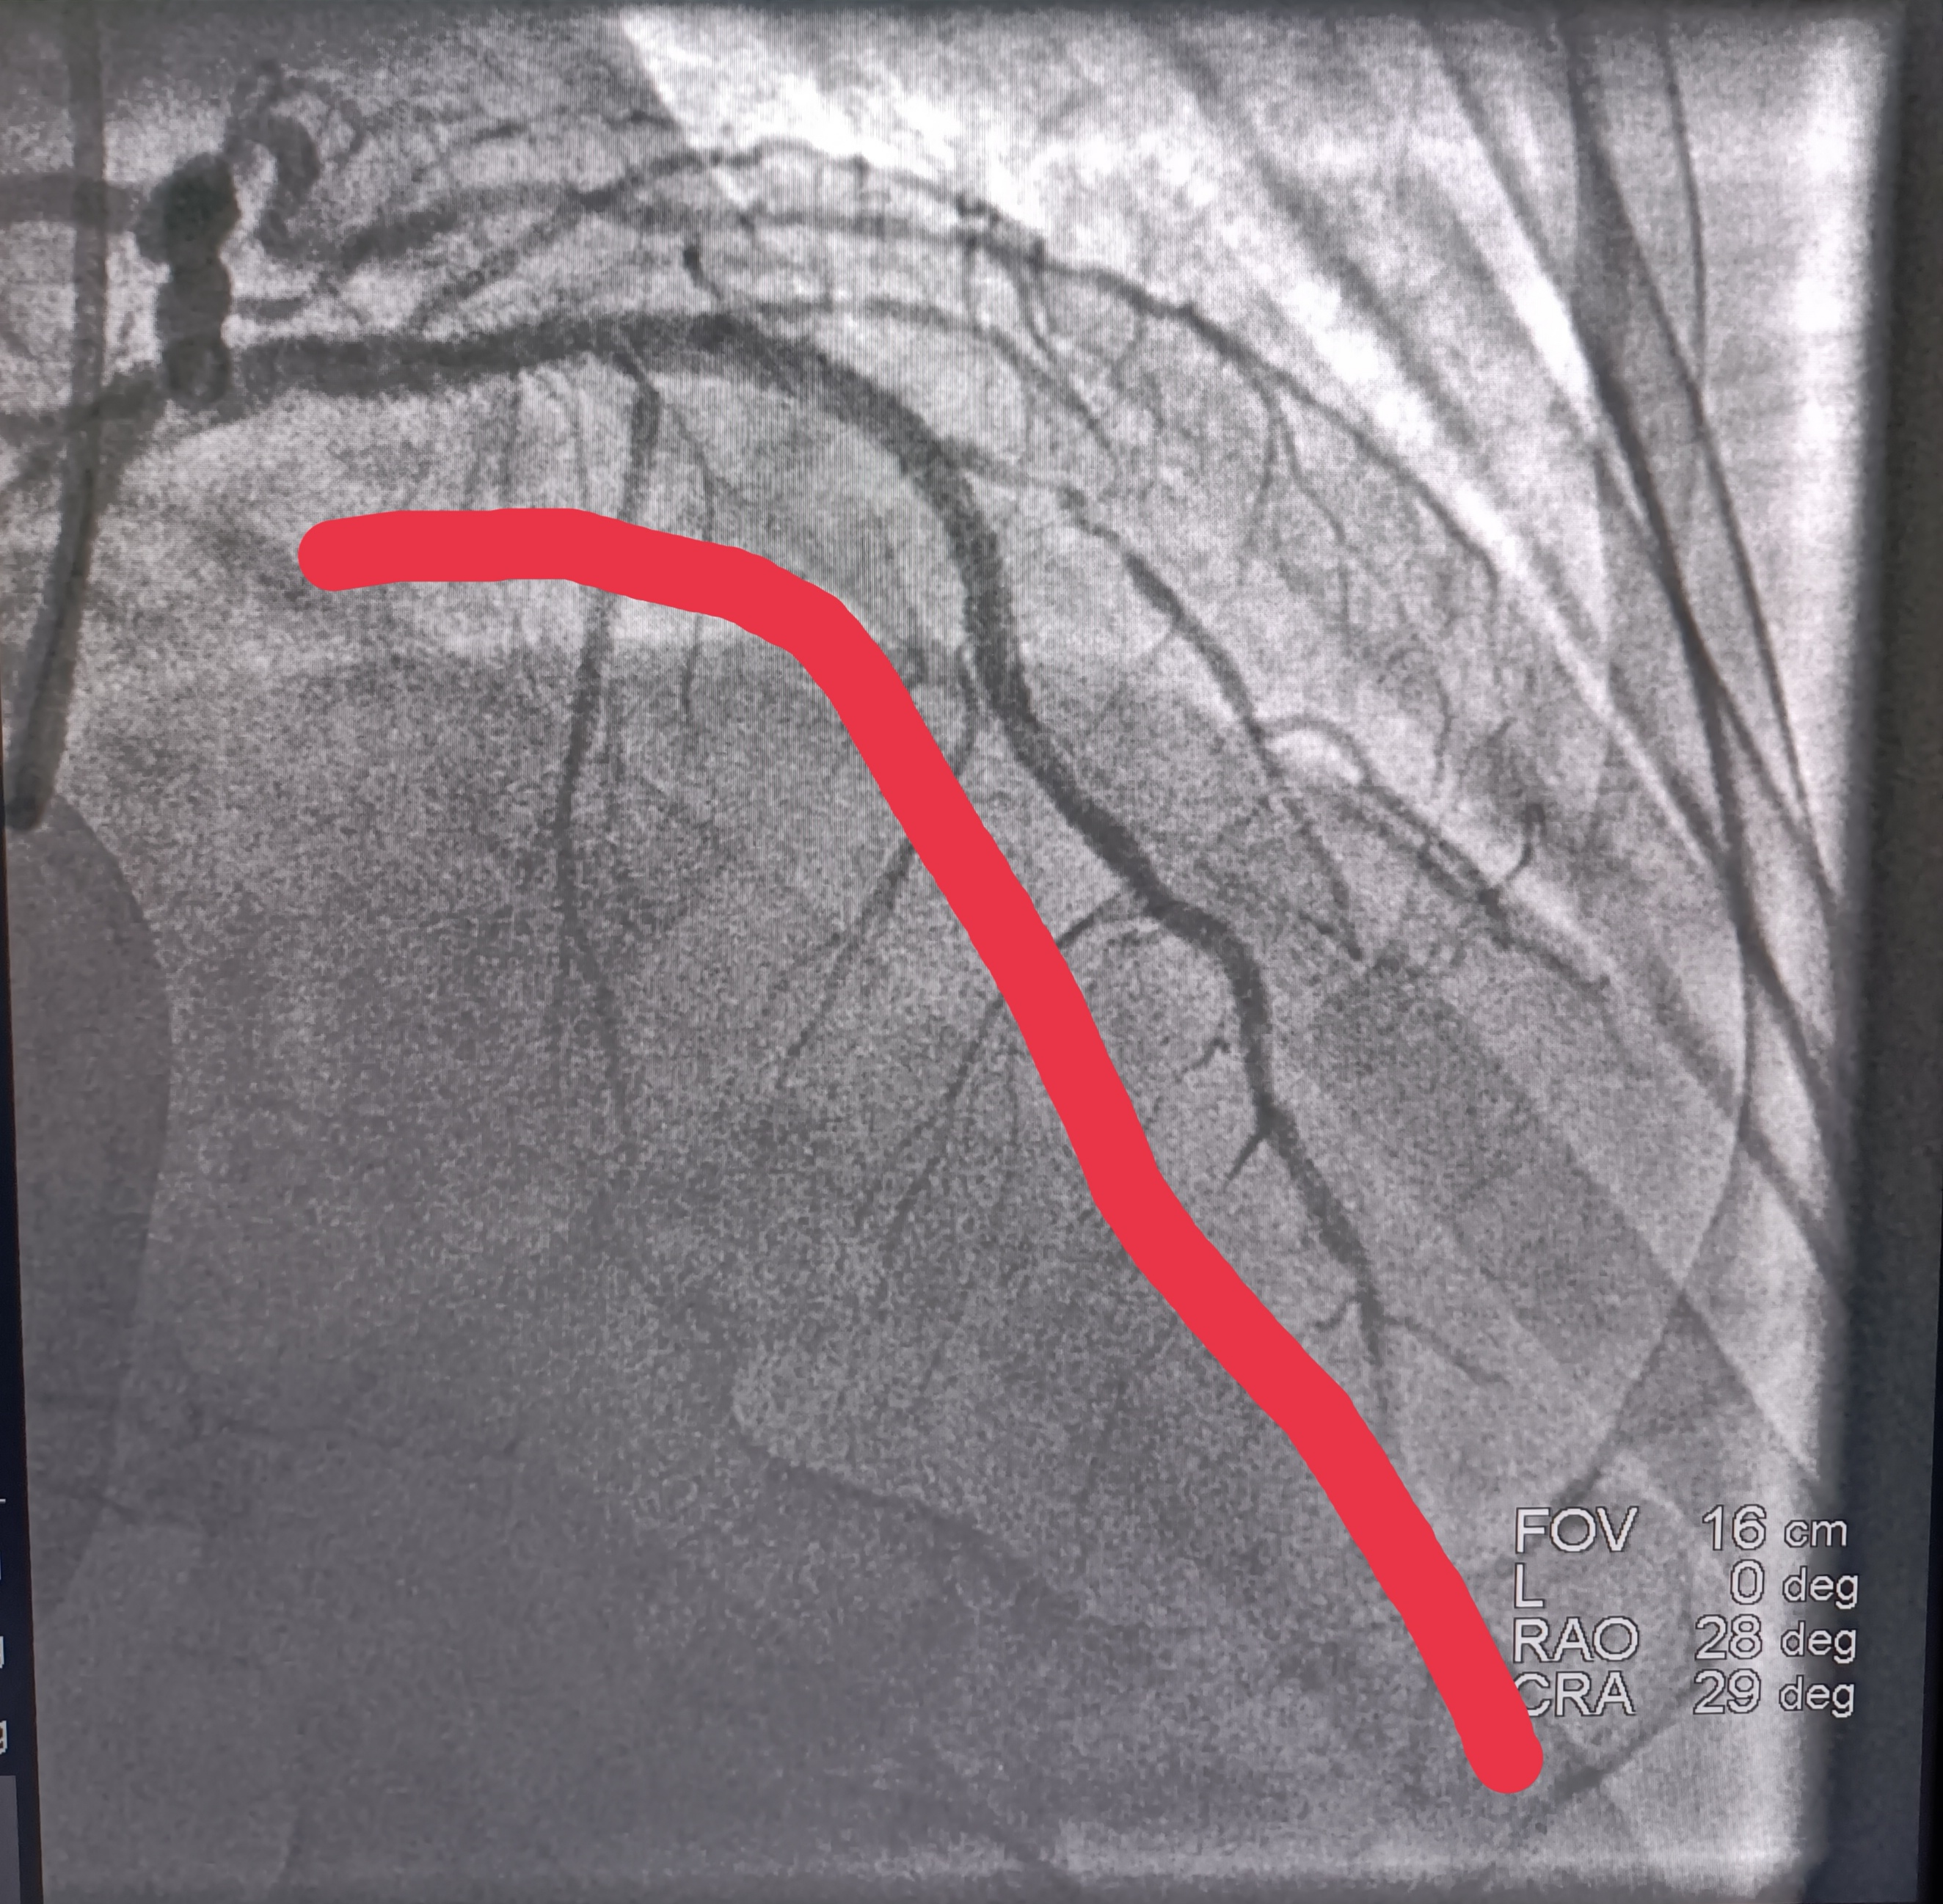

在患者被推到導管室門口,患者心髒再次室顫,醫生再次電擊除顫;這時候導管室早在20分鍾前做好了壹切手術准備。患者造影很順利,造影顯示心髒做大血根部堵塞,經過導絲通過,球囊擴張,血流顯影,支架植入,血流恢復。

手術前

手術後